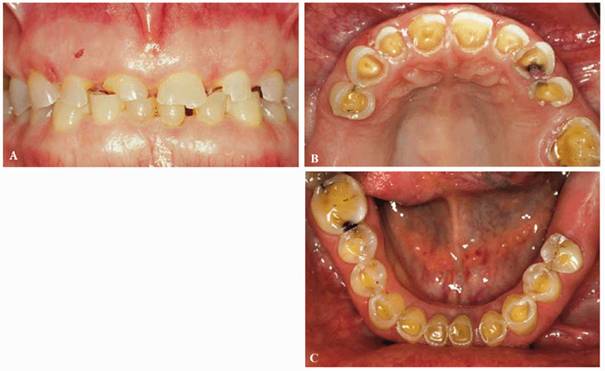

The most conservative restoration of Class V defects is composite resin

procedure can be seen in Figures 17-8A

and B 17-8C 17-8D 17-8E 17-8F 17-8G 17-8H and I, which show a 45-year-old man with

evidence of gingival and incisal abrasion, erosion, and abfraction. It is

enable a stronger bonded restoration.

Figure 17-8A and B: This 45-year-old man shows extreme tooth loss due to combination lesions both gingivally and incisally of abrasion, erosion, and abfraction.